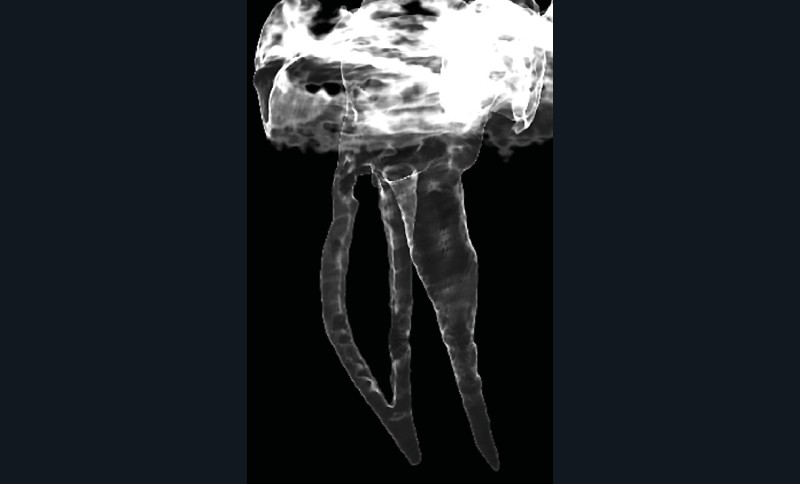

La mise en forme doit également s’adapter aux singularités anatomiques. Pour ce cas clinique, le canal mésio-lingual a été mis en forme en premier jusqu’à la longueur de travail. Puis le test du cône a été réalisé (fig. 4 et 5) afin de voir si les deux canaux se rejoignaient. Ces deux canaux se rejoignant à 3 mm de l’apex, le canal mésio-vestibulaire a été mis en forme à sa longueur de travail moins 3 mm afin d’éviter la zone de confluence et le risque accru de fracturer un instrument. De plus, cette mise en forme longueur de travail-3 mm a son importance pour la précision de l’obturation et l’ajustage des cônes. Pour le canal distal, qui était un canal « en 8 », nous appliquons le même raisonnement que pour les canaux mésiaux, avec un canal principal, test du cône, et ajustage des maîtres-cônes (fig. 6).